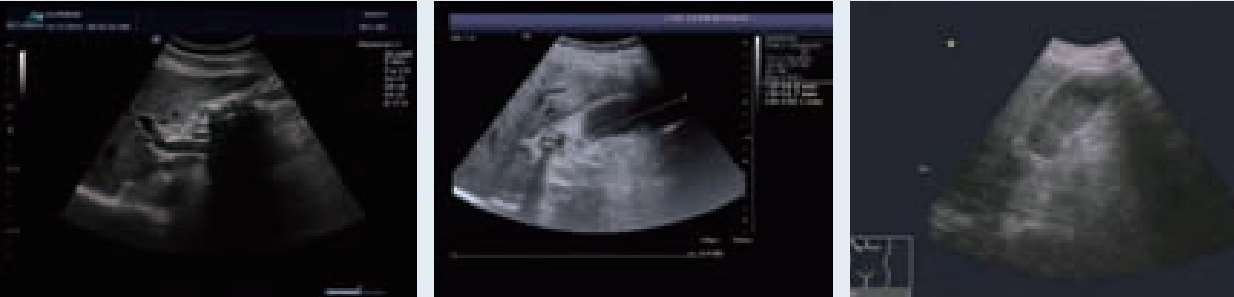

第三章

经皮经肝穿刺取石术原理